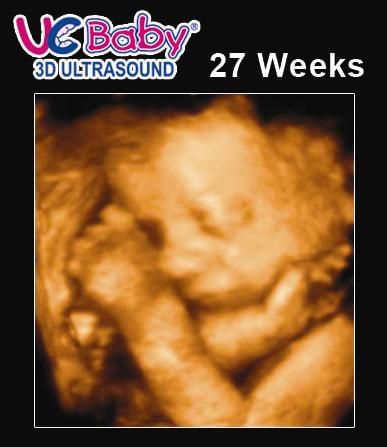

Pregnancy Week 27 3d Ultrasound

Pregnancy week 27 3d ultrasound. 27 weeks pregnant ultrasound inside your 27 weeks belly baby is practicing inhaling and exhaling with their rapidly developing lungs. Normal 25 week pregnancy and ultrasound the useful guide. Unfortunately thats not the only thing thats swelling. An ultrasound at 27 weeks will show a baby in various actions.

3dultrasound 27weekspregnant pregnantduringapandemic hey friends. Two weeks ago your belly was a soccer ball and by 27 weeks pregnant your uterus has swelled to the size of a basketball. Your list of pregnancy symptoms at 27 weeks includes. Week 27 ultrasound now that the baby to be is growing rapidly its harder to get a complete profile in the womb he just doesnt fit in the picture anymore.

Your baby is likely moving quite a bit these days and its important that you do too opting for safe activities if exercise is advised of course. Heshe might be engaged in activities such as yawning punching kicking blinking of eyes and sucking thumbs. Normal 26 week pregnancy and ultrasound the useful guide. Welcome to week 27 of your pregnancy the final week of your second trimester.

Fetal heartbeat at week 27 pregnancy is strong enough to be heard in an ultrasound. What you should expect. This would also be the time where doctors would be looking to see if you have one heartbeat or multiple to see how many babies you are pregnant with. Todays vlog is a very exciting one.